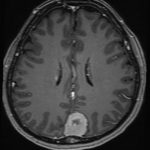

No.’25_108 手術前1

No.’25_108 手術前2